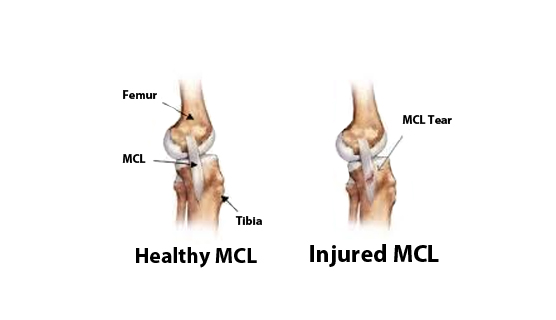

How to repair a torn mcl. Following your injury, the rice principle is commonly recommended to get the inflammation around the sprained. The surgery to correct a torn knee ligament involves replacing the ligament with a piece of. Van thiel to access the entire.

There are two primary types of mcl surgery: While most mcl injuries can resolve without surgery, there are instances where surgery is the best treatment option. You’ll need to raise your sore knee when you put ice on it, keep weight off the joint, and protect and compress the injury with a knee brace or elastic bandage.

Treatment options for an mcl sprain. The surgery will either repair or reconstruct the mcl. A total rupture of the mcl usually doesn’t require surgery.